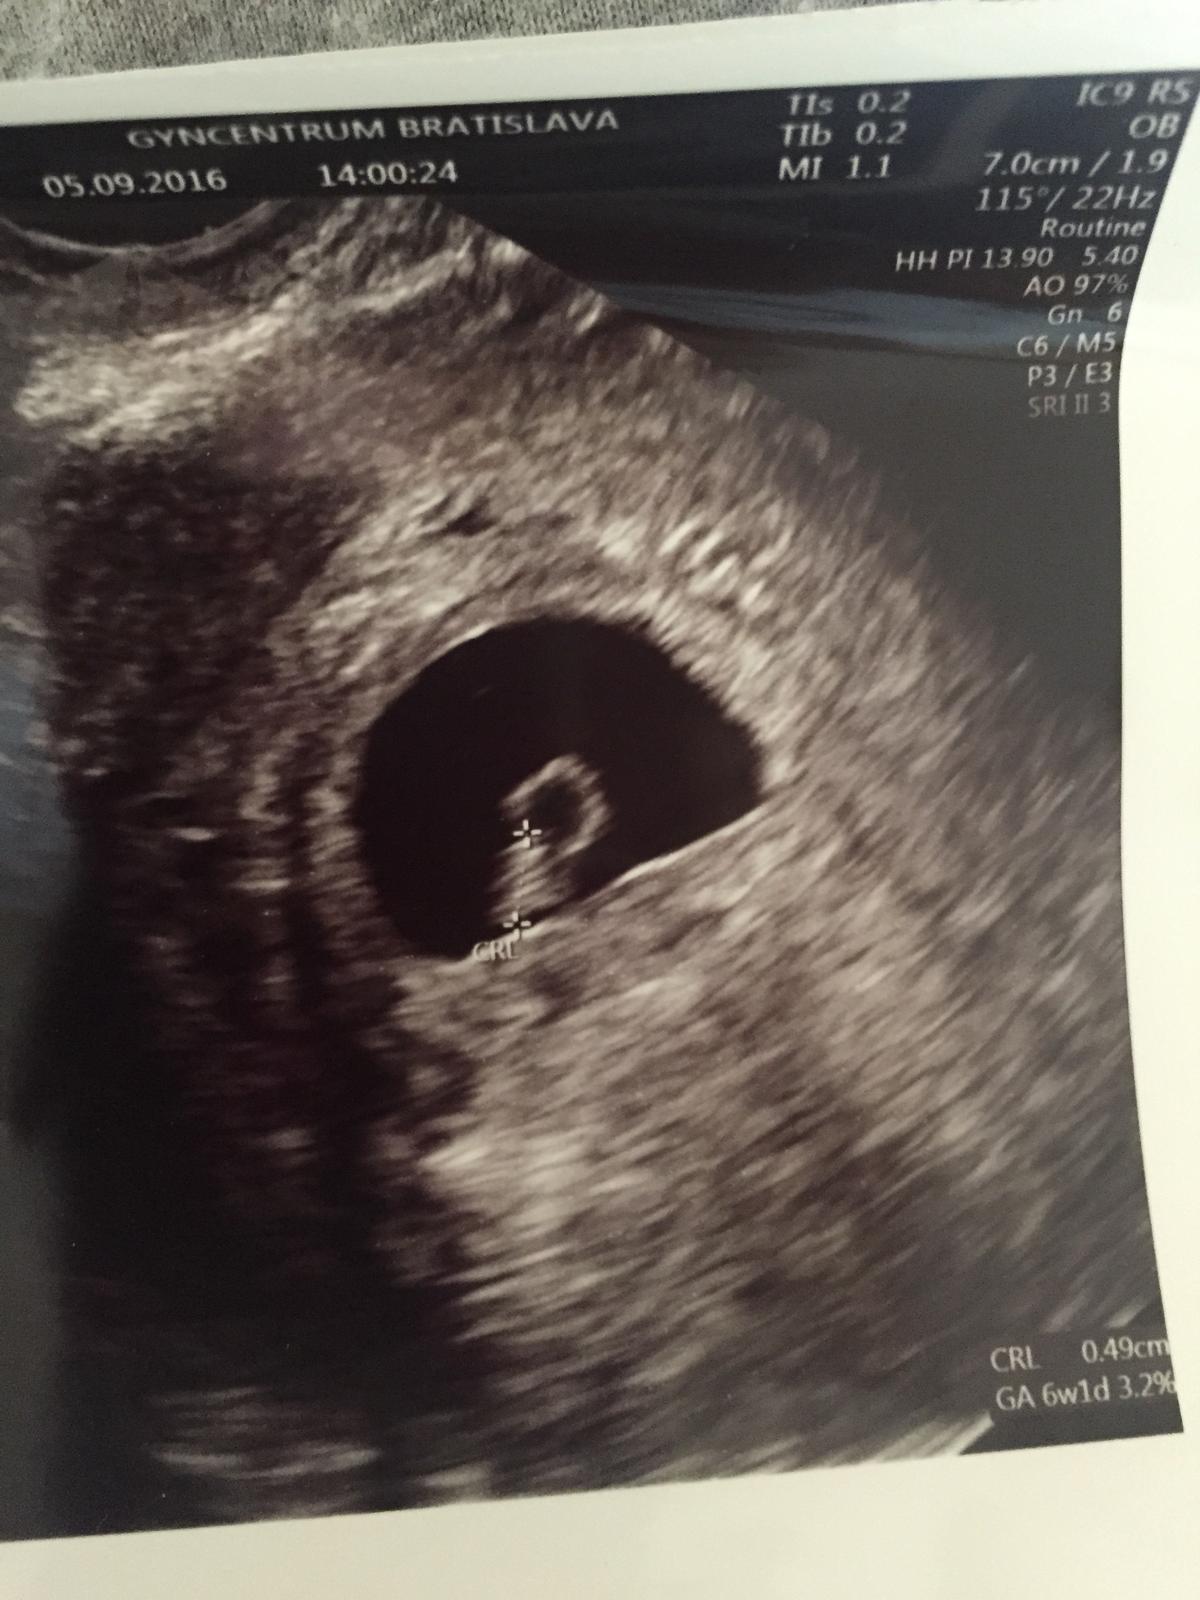

ahoj ja som ti test nerobila a otehotnela som zrejme hned po menstruacii alebo možno aj počas nej :D nafukla som sa prsia ma boleli a ked neprisla dalsia šla som hned ku gyn bola som u nej v utorok tento tyžden a som 6tyž + 5den 🙂 bije nam srdiecko a mame 6,4mm 🙂 zobrala mi ster na cytologiu a objednala ma na 4.10. na dva krat aj krv na rozne testy aj na tehotensku knižku 🙂 + mi napisala vitaminy ladeevita a duphaston 🙂